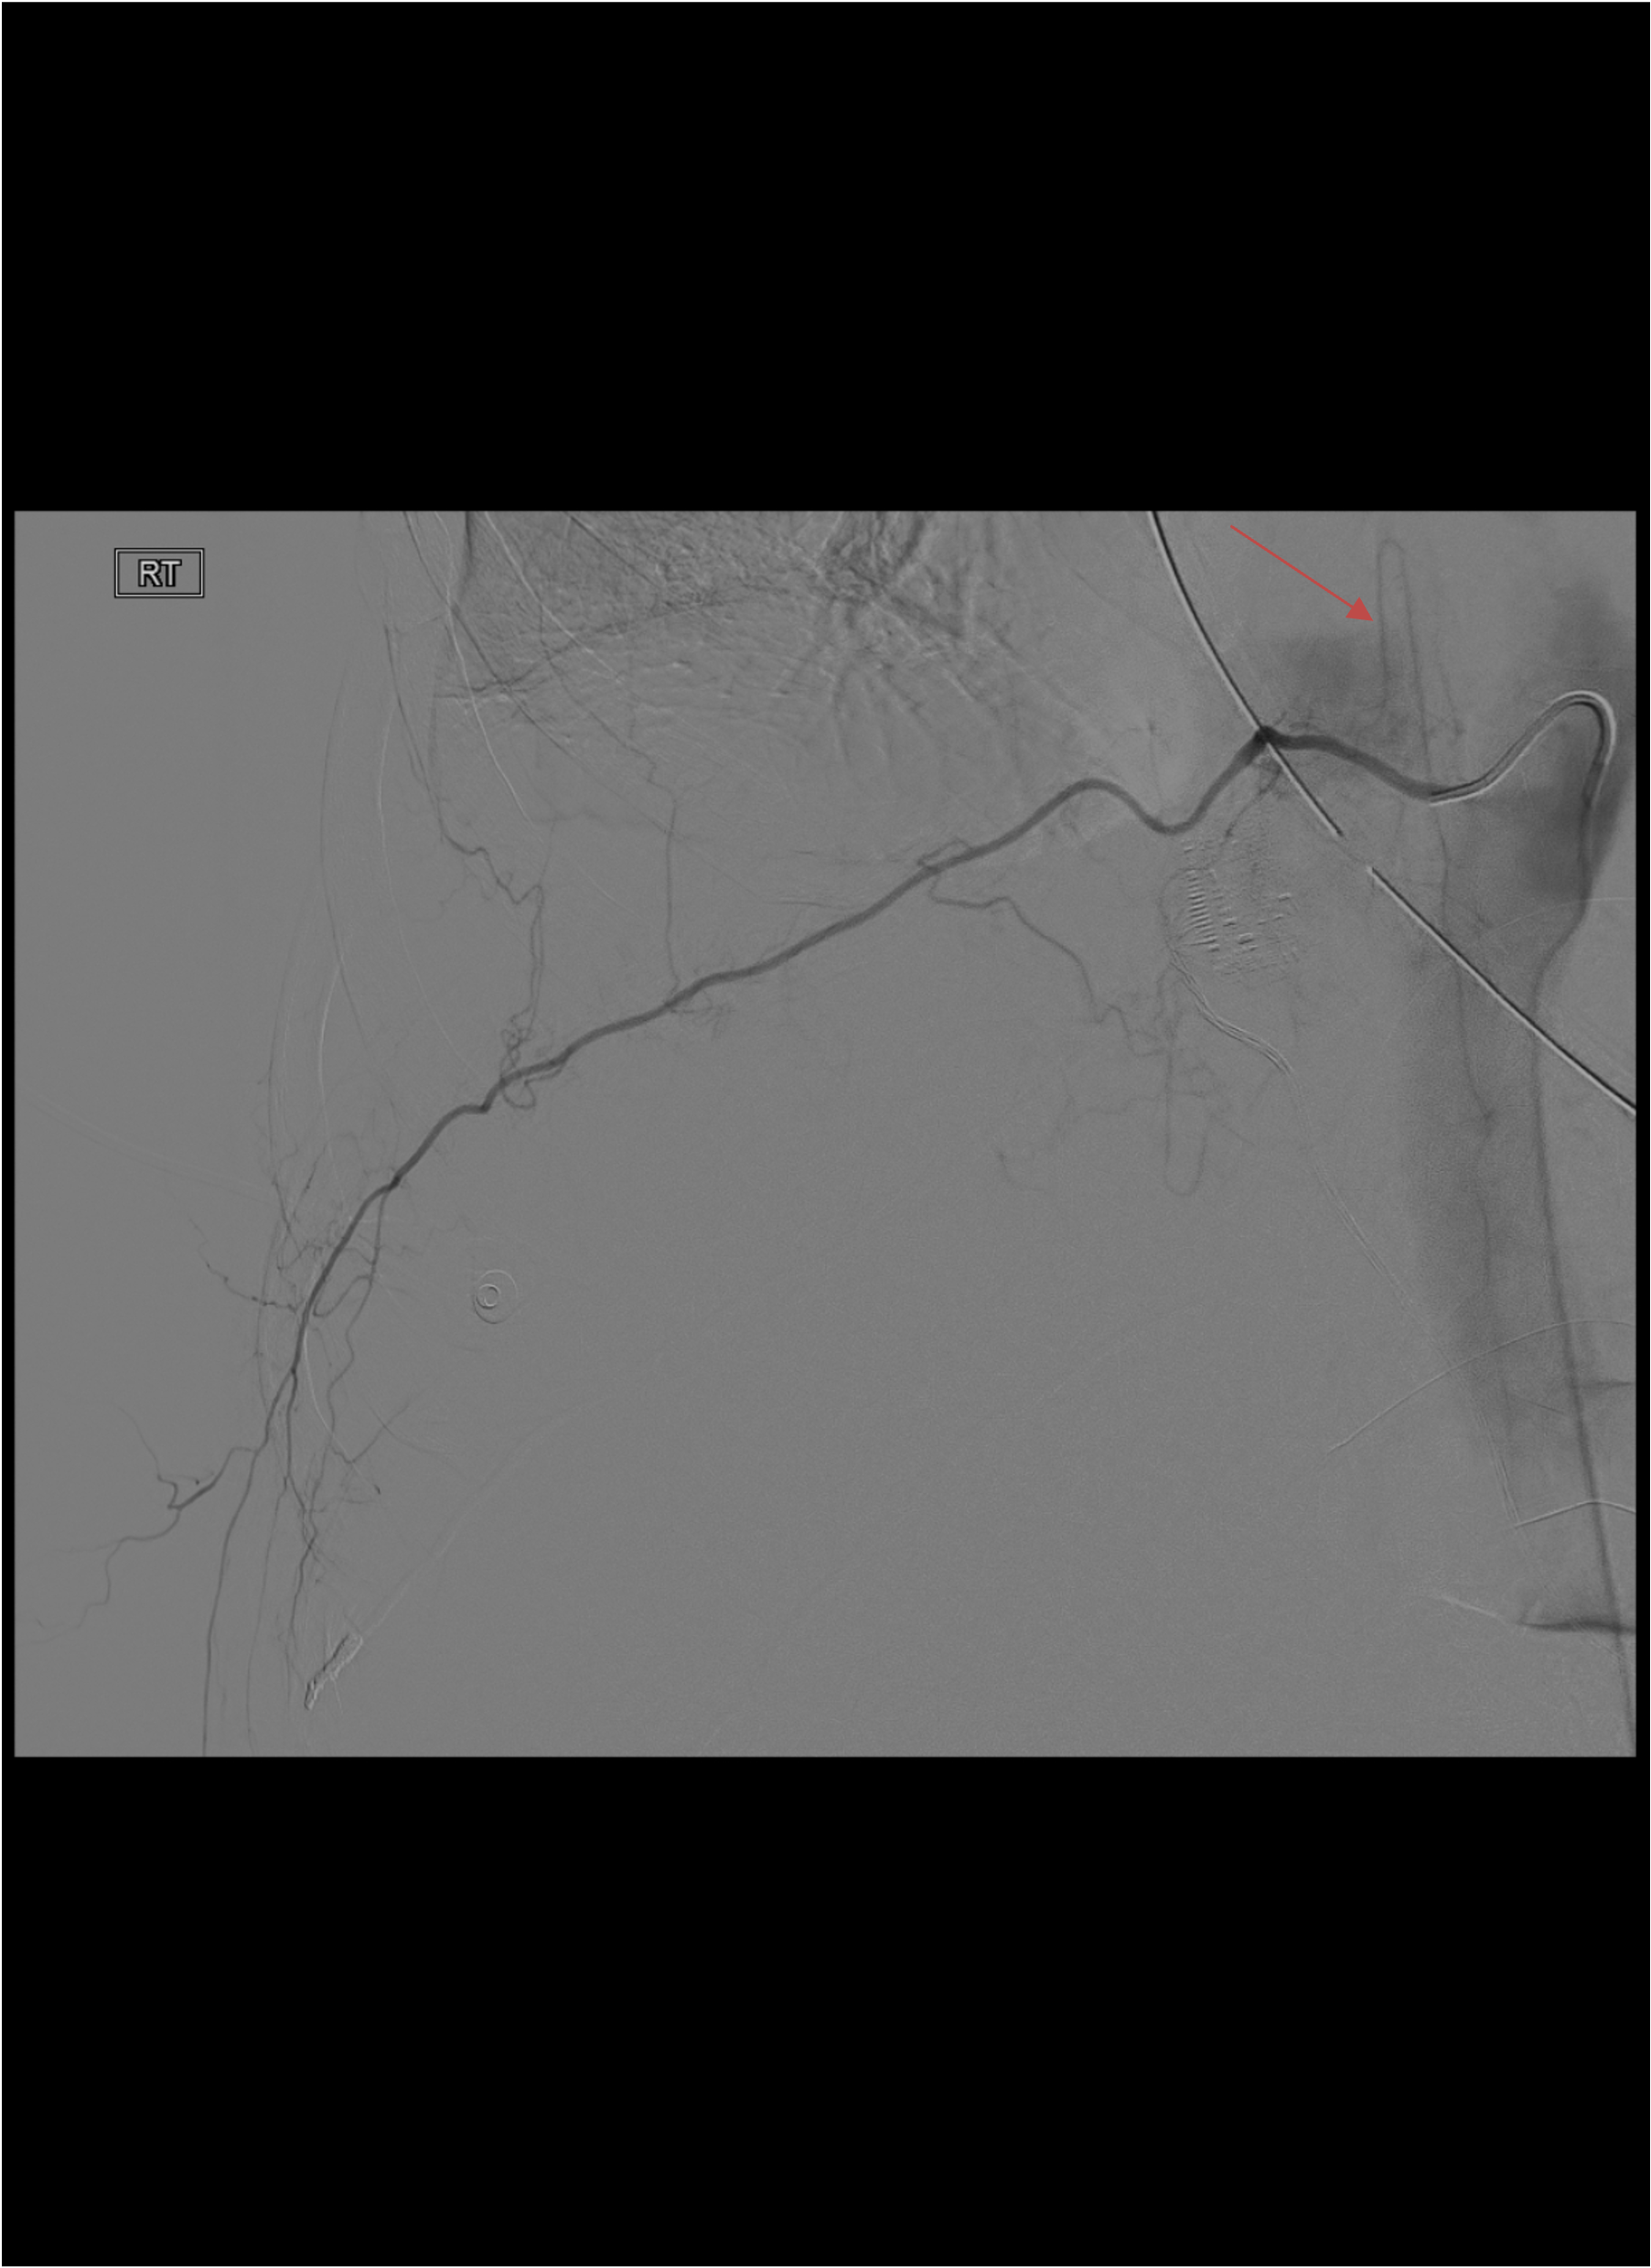

CRITICAL — Anterior Spinal Artery

- The anterior spinal artery can arise from a bronchial artery or intercostal artery — embolization causes spinal cord infarction and paralysis

- Look for the characteristic “hairpin” loop on selective angiography — a small branch coursing medially toward the spinal canal with a sharp turn

- If spinal artery is visualized: ABORT embolization of that vessel. Use microcatheter to achieve more distal purchase beyond the spinal artery origin, or abandon that artery entirely.

- Provocative testing with intra-arterial lidocaine or short-acting barbiturate can detect occult spinal artery supply

Spinal Artery Hairpin Sign

- Small branch coursing medially toward the spinal canal

- Makes a sharp “hairpin” turn as it joins the anterior spinal artery

- If seen: STOP — do NOT embolize that vessel from this position

- Advance microcatheter distal to spinal artery origin or abandon vessel

Anterior Spinal Artery Seen on Selective Angiogram

ABORT embolization of that artery from current catheter position. Options: advance microcatheter beyond spinal artery origin to achieve distal purchase and embolize from there (only if safe distance confirmed), or abandon that vessel entirely. Never embolize proximal to a visible spinal artery origin. Document finding. Consider provocative testing with intra-arterial lidocaine if occult spinal supply is suspected in other vessels.